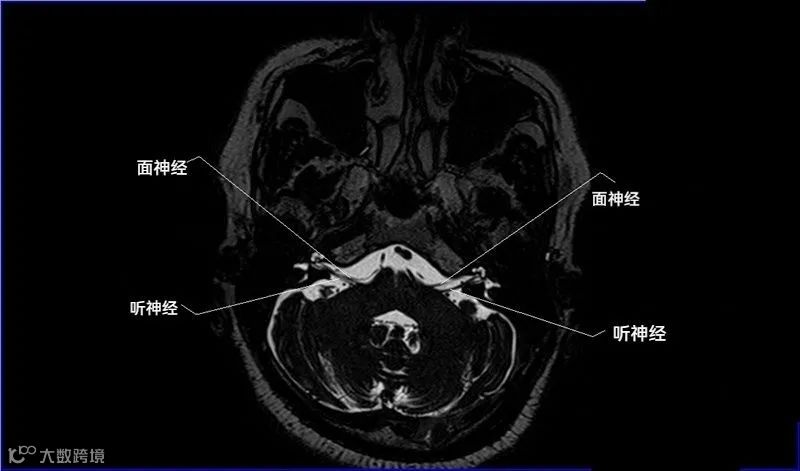

十二对脑神经口诀

一嗅二视三动眼,四滑五叉六外展,

七面八听九舌咽,迷走及副舌下全。